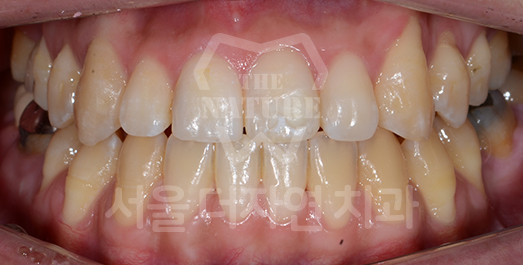

Crowding (Supernumerary / Overlapping Teeth) Solution

Crowding occurs when there is insufficient space for teeth to erupt into proper position.

If left untreated for a prolonged period, inadequate brushing access leads to food impaction between teeth

and a significantly elevated risk of dental caries.

As crowding is also a contributing factor to periodontal disease,

orthodontic correction is strongly recommended.

BEFORE: 2020.06.11

AFTER: 2023.02.02